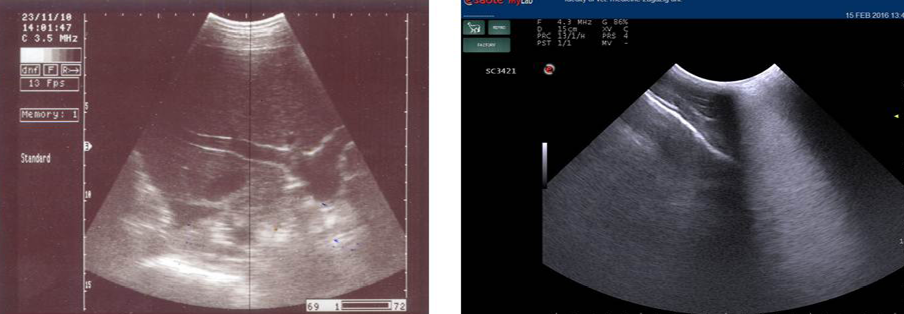

Ultrasonography image of normal liver appeared as homogenous hypo-echogenic structure (a) and that of pregnancy toxemic goat (b), notice the increased echogenicity of the liver “arrow” and faint appearance of hepatic vasculature.